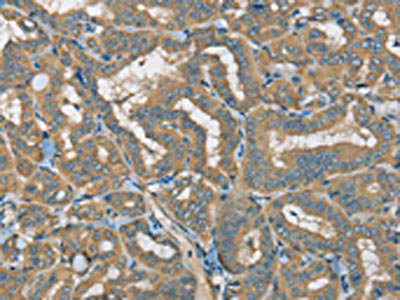

The image on the left is immunohistochemistry of paraffin-embedded Human thyroid cancer tissue using CSB-PA985822(ATP2A3 Antibody) at dilution 1/30, on the right is treated with synthetic peptide. (Original magnification: ×200)

The image on the left is immunohistochemistry of paraffin-embedded Human liver cancer tissue using CSB-PA985822(ATP2A3 Antibody) at dilution 1/30, on the right is treated with synthetic peptide. (Original magnification: ×200)